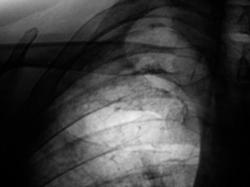

Произведено дообследование.

ИзображениеИзображениеИзображение